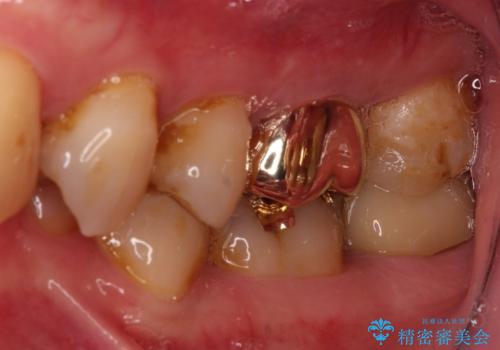

根管治療後に、歯根にまで及んでしまった破折部分を適切な位置に変更するため、歯槽骨の削除を伴う外科処置を行い、その後補綴治療を行うこととしました。

強い咬合力により歯が破折したため、補綴物は歯へのダメージの最も少ないゴールドクラウンを選択しました。